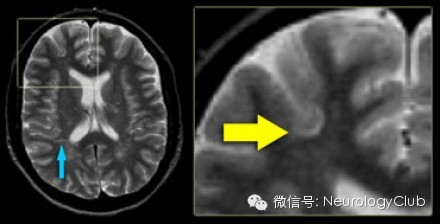

第四方面:皮质下白质病变

1、通常累及U形纤维

2、缺血性疾病以脑皮质为基底的楔形分布不累及U形纤维,可与鉴别